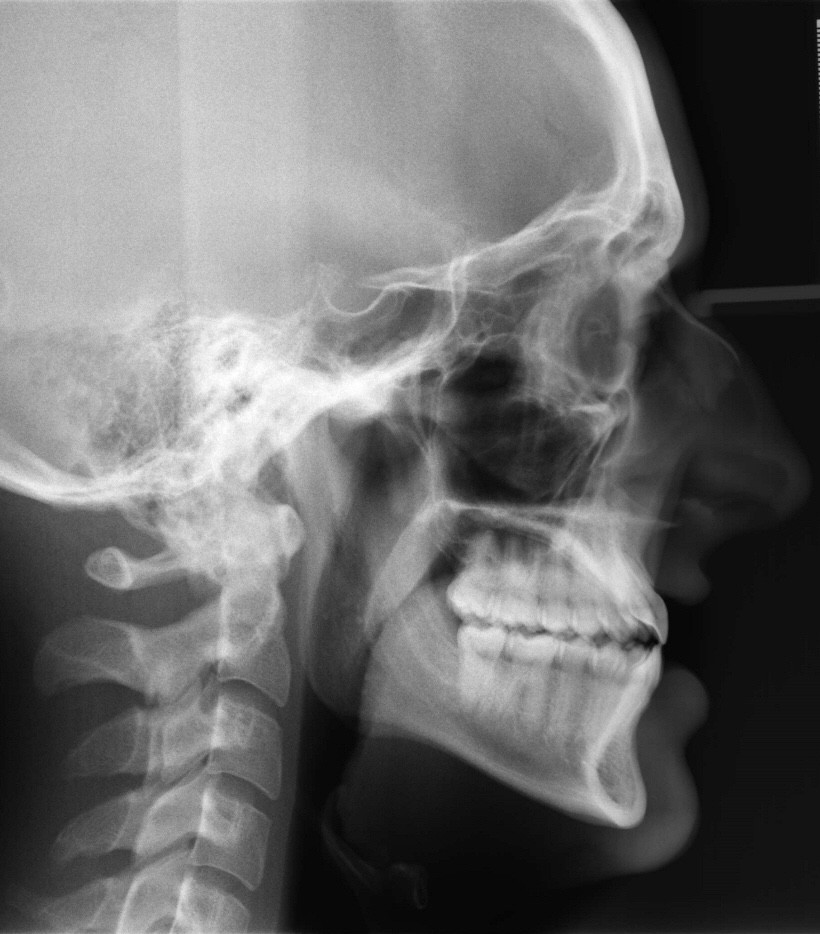

Initial treatment

X-RAYS